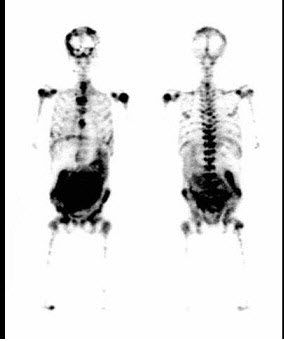

54、多项选择题

男,71岁,无诱因左大腿乏力疼痛半个月,无恶性肿瘤、发热及外伤史,体检无包块。行骨显像如图,CT示股骨溶骨性破坏,无软组织肿块。可能的诊断是()

A.左侧股骨上段及右侧股骨中段骨恶性改变征象

B.原发骨肿瘤并骨转移

C.多发性骨髓瘤

D.骨巨细胞瘤

E.可能是原发的骨肿瘤